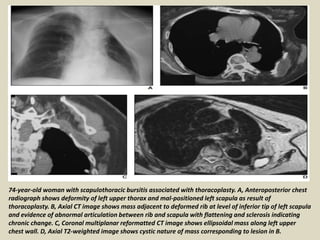

74-year-old woman with scapulothoracic bursitis associated with thoracoplasty. A, Anteroposterior chest

radiograph shows deformity of left upper thorax and mal-positioned left scapula as result of

thoracoplasty. B, Axial CT image shows mass adjacent to deformed rib at level of inferior tip of left scapula

and evidence of abnormal articulation between rib and scapula with flattening and sclerosis indicating

chronic change. C, Coronal multiplanar reformatted CT image shows ellipsoidal mass along left upper

chest wall. D, Axial T2-weighted image shows cystic nature of mass corresponding to lesion in B.